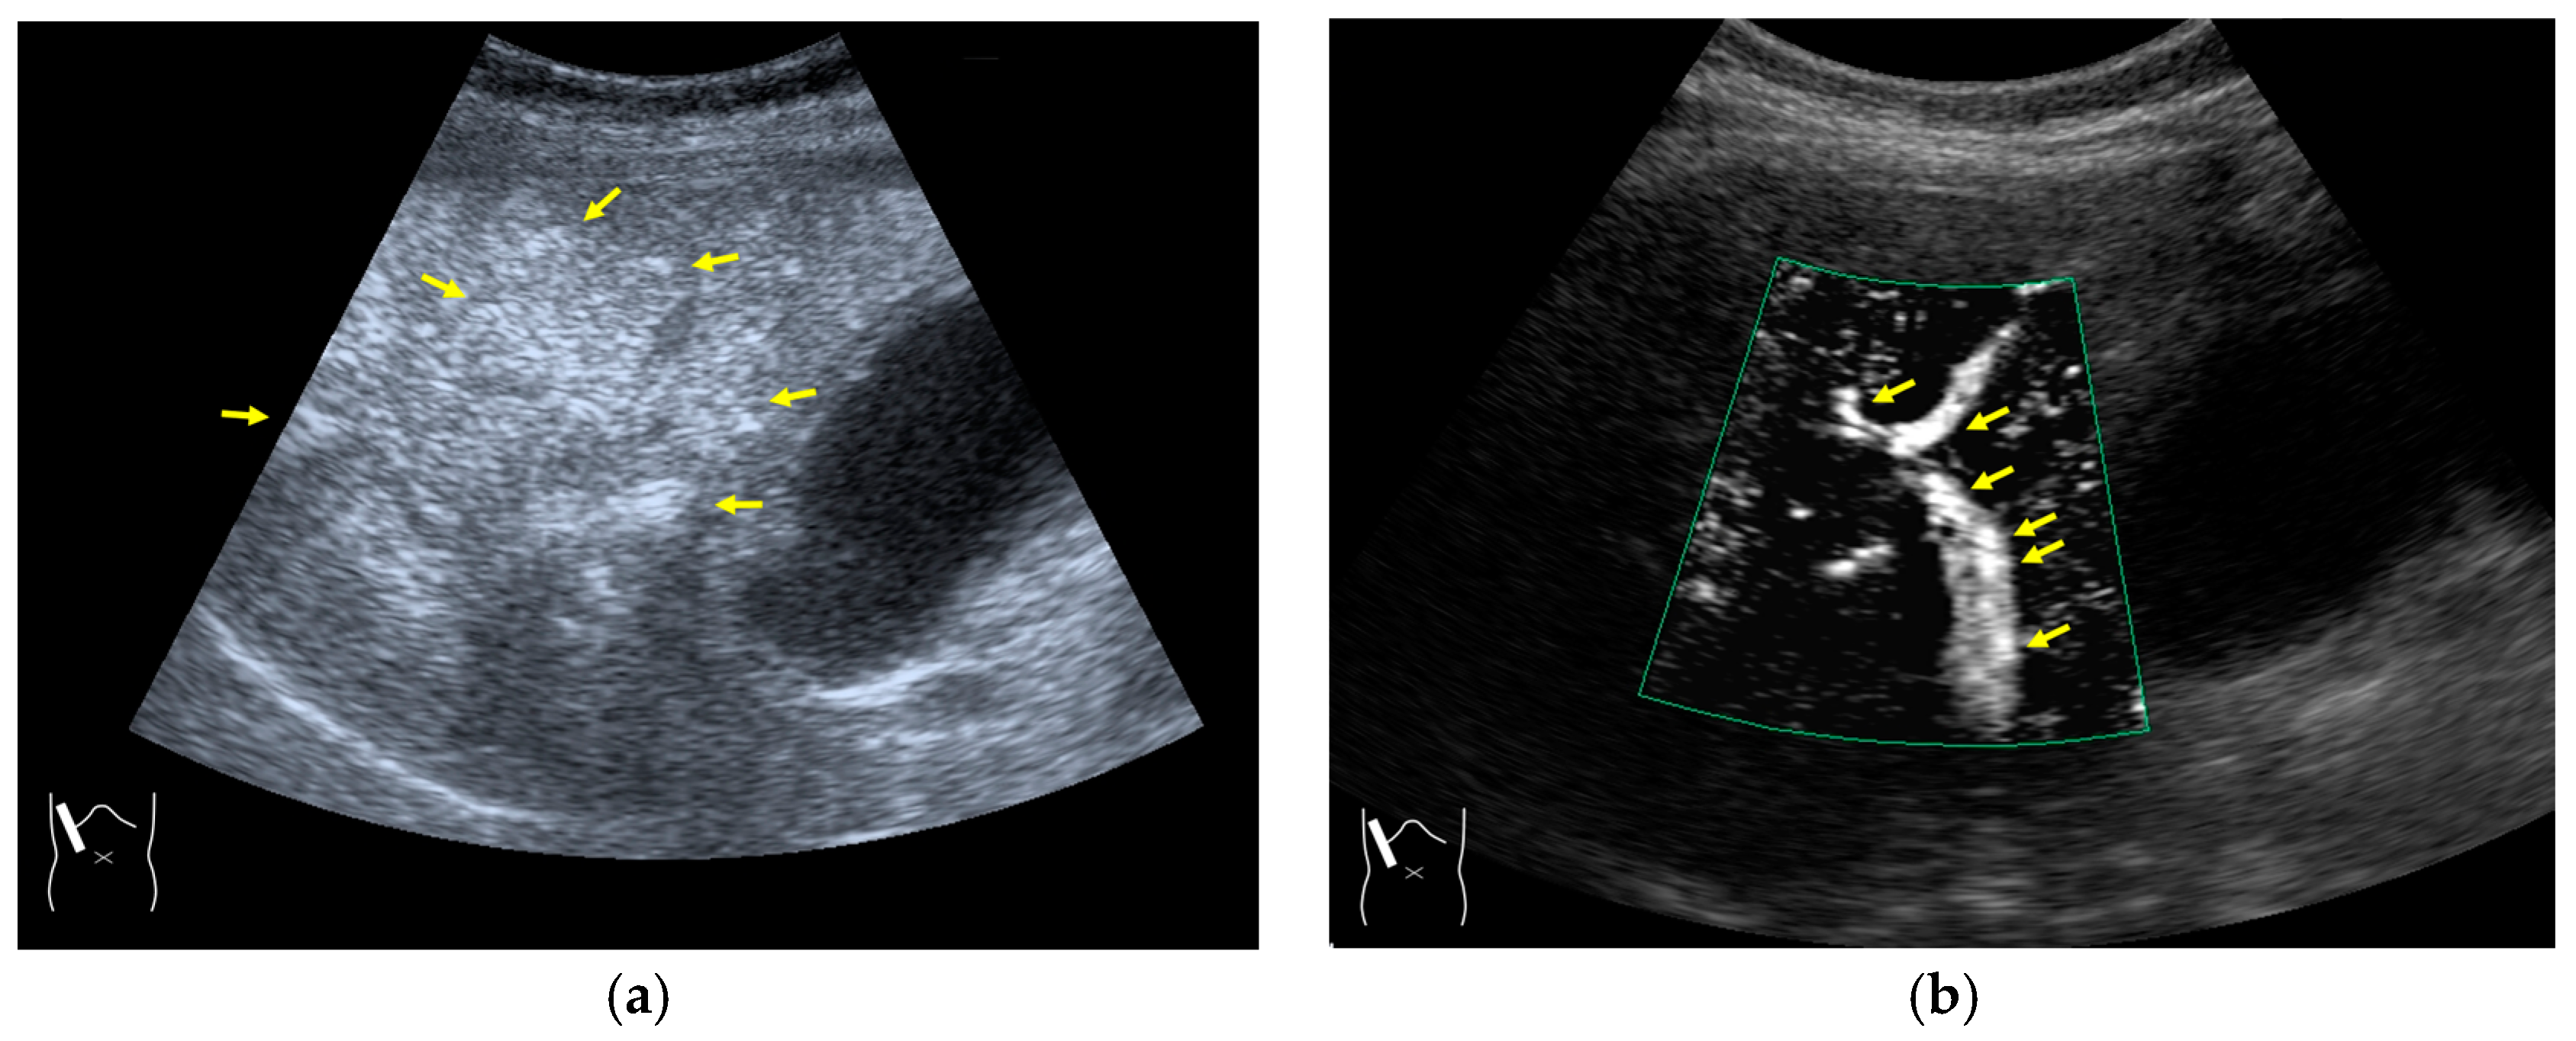

3.2.3. CEUS-Related Posterior Echo Enhancement

- Dietrich, C.F.; Mertens, J.C.; Braden, B.; Schuessler, G.; Ott, M.; Ignee, A. Contrast-enhanced ultrasound of histologically proven liver hemangiomas. Hepatology 2007, 45, 1139–1145. [Google Scholar] [CrossRef]

- Maturen, K.E.; Wasnik, A.P.; Bailey, J.E.; Higgins, E.G.; Rubin, J.M. Posterior acoustic enhancement in hepatocellular carcinoma. J. Ultrasound Med. 2011, 30, 495–499. [Google Scholar] [CrossRef] [PubMed]